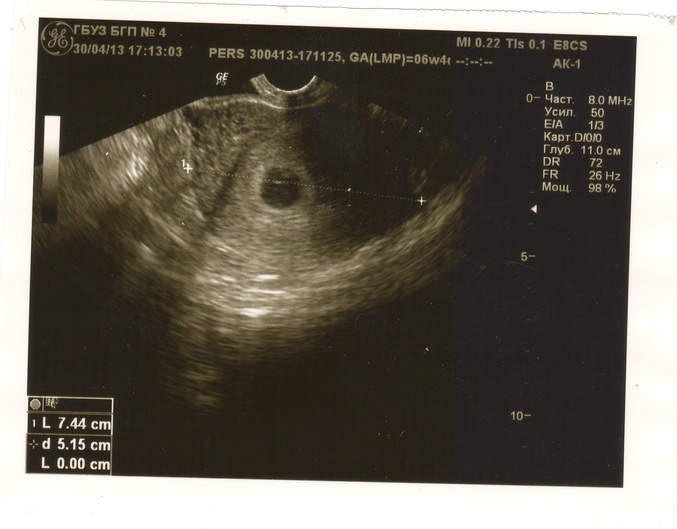

2 узи, 6 нд

Захожу, мне говорят, да вообщем-то уже и не обязательно (видимо потому что М не начались всё-таки). Смотрят, в полости матки вижу небольшой такой пузырик, спрашиваю, это плодное яйцо? Да, всё впорядке. Напечатали мне фотку. Счастью моему не было предела.